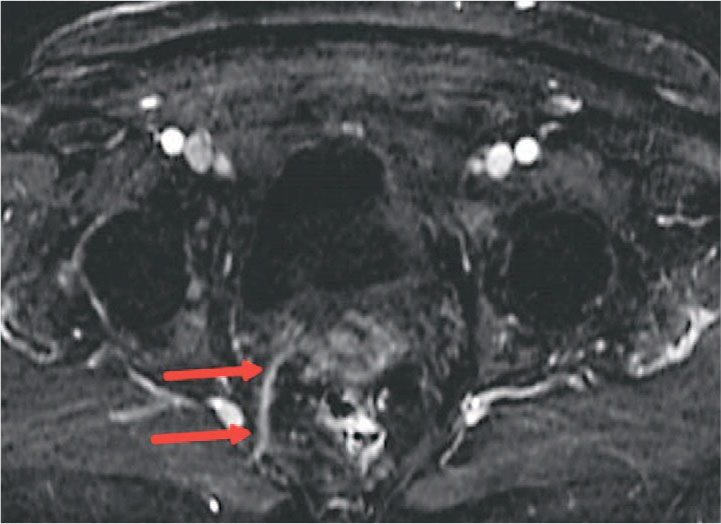

При выполнении МРТ органов малого таза с внутривенным контрастированием препаратом гадолиния спустя более 180 дней после оперативного вмешательства нити импланта с сформированным рубцом дифференцируется как тяж диаметром до 3-5 мм, следующий от сакроспинальной связки до шейки матки, без признаков отека на Т2-ВИ с подавлением сигнала от жира, с отчетливым равномерным накоплением контрастного препарата в позднюю венозную фазу, что характерно для рубцовой ткани (рис. 3-5).

Рис. 4. Пациентка Г. 72 года. МРТ органов малого таза. Т1-ВИ с подавлением сигнала от жира после внутривенного контрастирования – поздняя венозная фаза. Рубец на уровне импланта справа отчетливо равномерно накапливает контрастный препарат (стрелки)

Fig. 4. Patient G, 72 years old. MRI of the pelvic organs. T1-VI with fat signal suppression after intravenous contrast late venous phase. The scar at the level of the implant on the right side clearly uniformly accumulates contrast agent (arrows))

Дополнительные данные, полученные при МРТ органов малого таза с контрастированием, подтвердили отсутствие признаков выраженной воспалительной реакции или хронического отека в зоне имплантации, что свидетельствует о хорошей биосовместимости частично резорбируемого материала, что также ранее было продемонстрировано в экспериментальном исследовании. Визуализация импланта позволила зафиксировать его интеграцию в ткани тазового дна и замещение резорбируемого компонента соединительнотканными структурами. Данный факт позволяет утверждать, что количество нерезорбируемого компонента достаточно для поддержания сформированной соединительнотканной неосвязки.